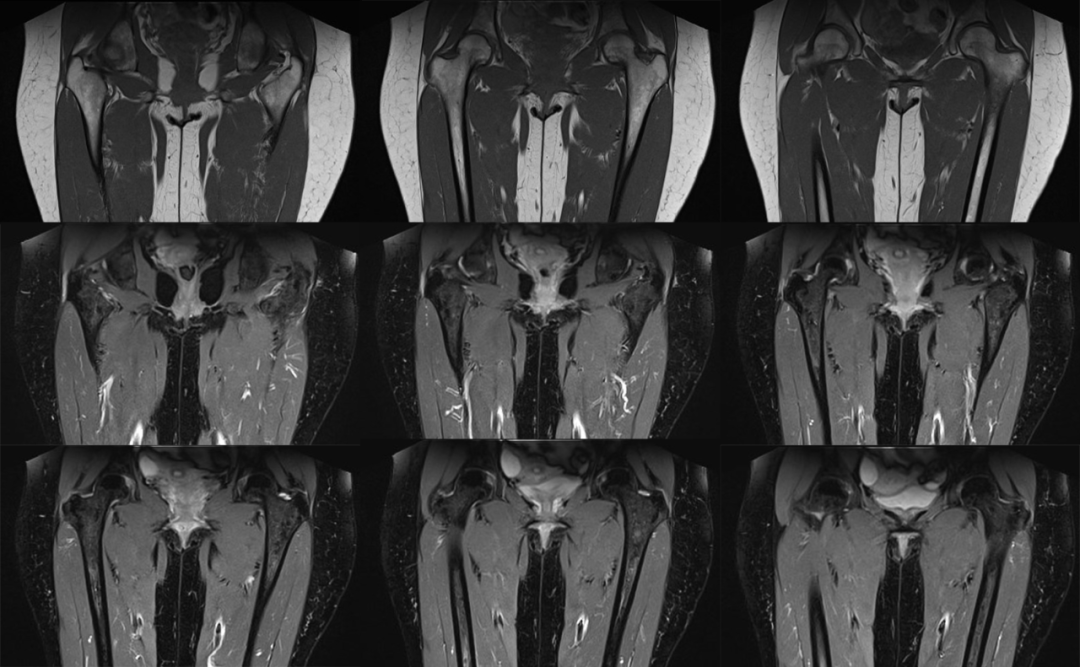

影像表现重点谈 MRI 表现:

1. 坐骨股骨间隙变窄,坐骨股骨间隙是坐骨结节外侧骨皮质到股骨小转子内侧骨皮质的最窄距离,正常坐骨股骨间隙正常人群组为 23±8 mm,若间隙﹤15 mm 可视为狭窄。

2. 股方肌间隙变窄,股方肌间隙是股方肌通过的最窄间隙,其后内侧边界是腘绳肌肌腱止点的外上表面,前外侧边界是髂腰肌肌腱或股骨小转子的后内侧表面,测量这两个边界之间的最短距离。正常股方肌间隙人群组为 12±4 mm,若间隙﹤8 mm 可视为狭窄。

3. 股方肌以位于坐骨股骨间隙最狭窄处的肌腹为中心出现水肿信号或挤压变形。

4. 其他表现还包括髂腰肌腱止点水肿、腘绳肌腱止点水肿或损伤、滑囊样组织形成。

5. 长期病变患者可出现股方肌脂肪浸润或肌萎缩。

测量方式:坐骨-股骨间隙测量 两侧相比右侧坐骨-股骨间隙缩小

股方肌位于狭窄处出现水肿